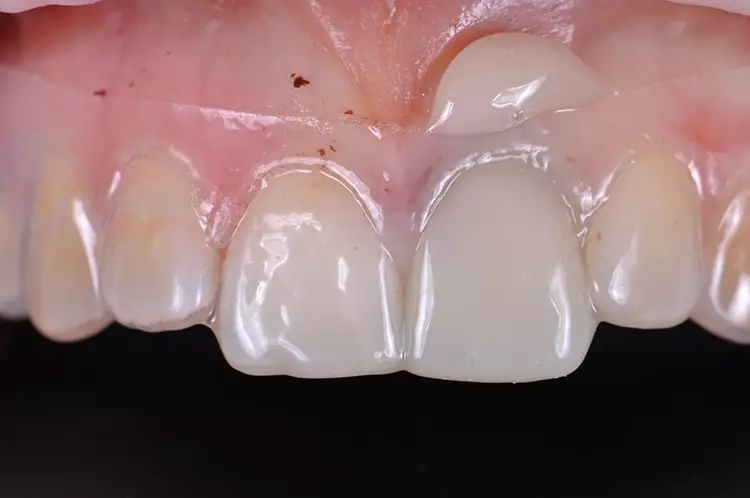

Im Rahmen des Erstgespräches berichtete die junge Patientin von einem Sturzereignis, bei dem der Schneidezahn frakturierte. Ihr damaliger Zahnarzt führte eine Wurzelkanalbehandlung durch und versorgte den Zahn mit einer Krone aus Lithiumdisilikat. Das anfänglich sehr ansprechende ästhetische Behandlungsergebnis hätte sich jedoch nach der Eingliederung mit der Zeit verändert und die Patientin stellte eine zunehmende Verfärbung der Frontzahnkrone fest (Abb. 2 und 3).

Dies kann aus einer nachträglich eingetretenen Verfärbung des devitalen Zahnes resultieren. Durch die sehr hohe Transluzenz der Glasphase einer Lithiumdisilikat-Restauration kann die dunkle Stumpffarbe durchschlagen und zu einem ästhetisch störenden „Grauschleier“ führen. In einem intensiven Beratungs- und Aufklärungsgespräch wurden der Patientin die Schwierigkeiten und Herausforderungen einer Einzelzahnkrone in der ästhetischen Zone bei einer hohen Lachlinie mit Exposition der Gingiva dargestellt.

Manche Details wie die Verfärbung der Gingiva wären nicht korrigierbar und verringerten die Vorhersagbarkeit eines optimalen ästhetischen Resultates. Die Neuversorgung dient der Verbesserung der ästhetischen Situation, eine perfekte Kopie des Zahnes 11 wird nicht zu erzielen sein, da die verfärbte Wurzel bestehen bleibe.

Trotz der aufgeführten Risiken und Unwägbarkeiten wünschte die junge Patientin eine Neuversorgung des Zahnes, um eine bestmögliche Ästhetik zu erreichen. Gleichzeitig sollten ihre natürliche Zahnfarbe und die individuelle Zahnstellung nicht verändert werden.